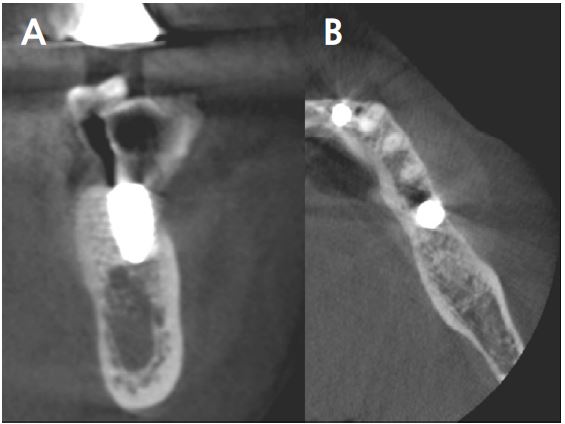

Clinical examination revealed grade 3 mobility with the gingival recession of the distal root of the left mandibular first molar (#36). Radiographic examination confirmed apically involved alveolar bone loss around the mandibular left first molar, however, at a sufficient distance from the mandibular canal (Fig. 1). It was determined that initial stability could be achieved in the apical area, and extraction and iARP were planned. The patient was instructed to rinse with 0.12% chlorhexidine digluconate solution (hexamedine; Bukwang, Seoul, Korea) for 2 min for oral disinfection. The mandibular left first molar was extracted using luxators and extraction forceps under local anesthesia with 2% lidocaine containing 1:80,000 epinephrine (Huons Lidocaine; Huons, Seoul, Korea) (Fig. 2A, 2B). After debridement of granulation tissues and irrigation with sterile normal saline solution, immediate implant placement (TS III 5.0 × 8.5 mm; OSSTEM, Seoul, Korea) was performed (Fig. 2C). The implant was placed 1 mm apical to the lingual socket wall, and the buccal side showed the exposure of two threads of the fixture (Fig. 2D). The implant stability quotient (ISQ) value at 1st surgery was 63. A gap between the implant surface and extraction socket wall and exposed buccal implant thread was filled with deproteinized bovine bone mineral (DBBM) (Bio-Oss®; Geistlich Pharma AG, Wolhusen, Switzerland) and covered with a native bilayer collagen membrane (NBCM) (Bio-Gide®; Geistlich Pharma AG) in a double-layer fashion (Fig. 2E). Subsequently, the hidden X suture and horizontal mattress suture (6-0 Ethilon; Ethicon, Cincinnati, OH, USA) were placed over the NBCM without the intention of primary wound closure (Fig 2F, 2G). Fourteen days after surgery, the patient returned for suture removal and postoperative examination. Healing of the depressed soft tissue above the extraction socket was observed, and a delayed healing pattern of the soft tissue with exposure of the cover screw was observed even after 4 weeks (Fig. 2H, 2I).

At 20 months follow-up, the cone beam computed tomography (CBCT) paraxial view showed that the buccal side of the fixture was adjacent to the outer border of the buccal bone plate (Fig. 5). However, the implant buccal probing depth (PD) did not exceed 4 mm, and the condition was maintained without any complications for 20 months after prosthesis placement (Fig. 6A, 6B).